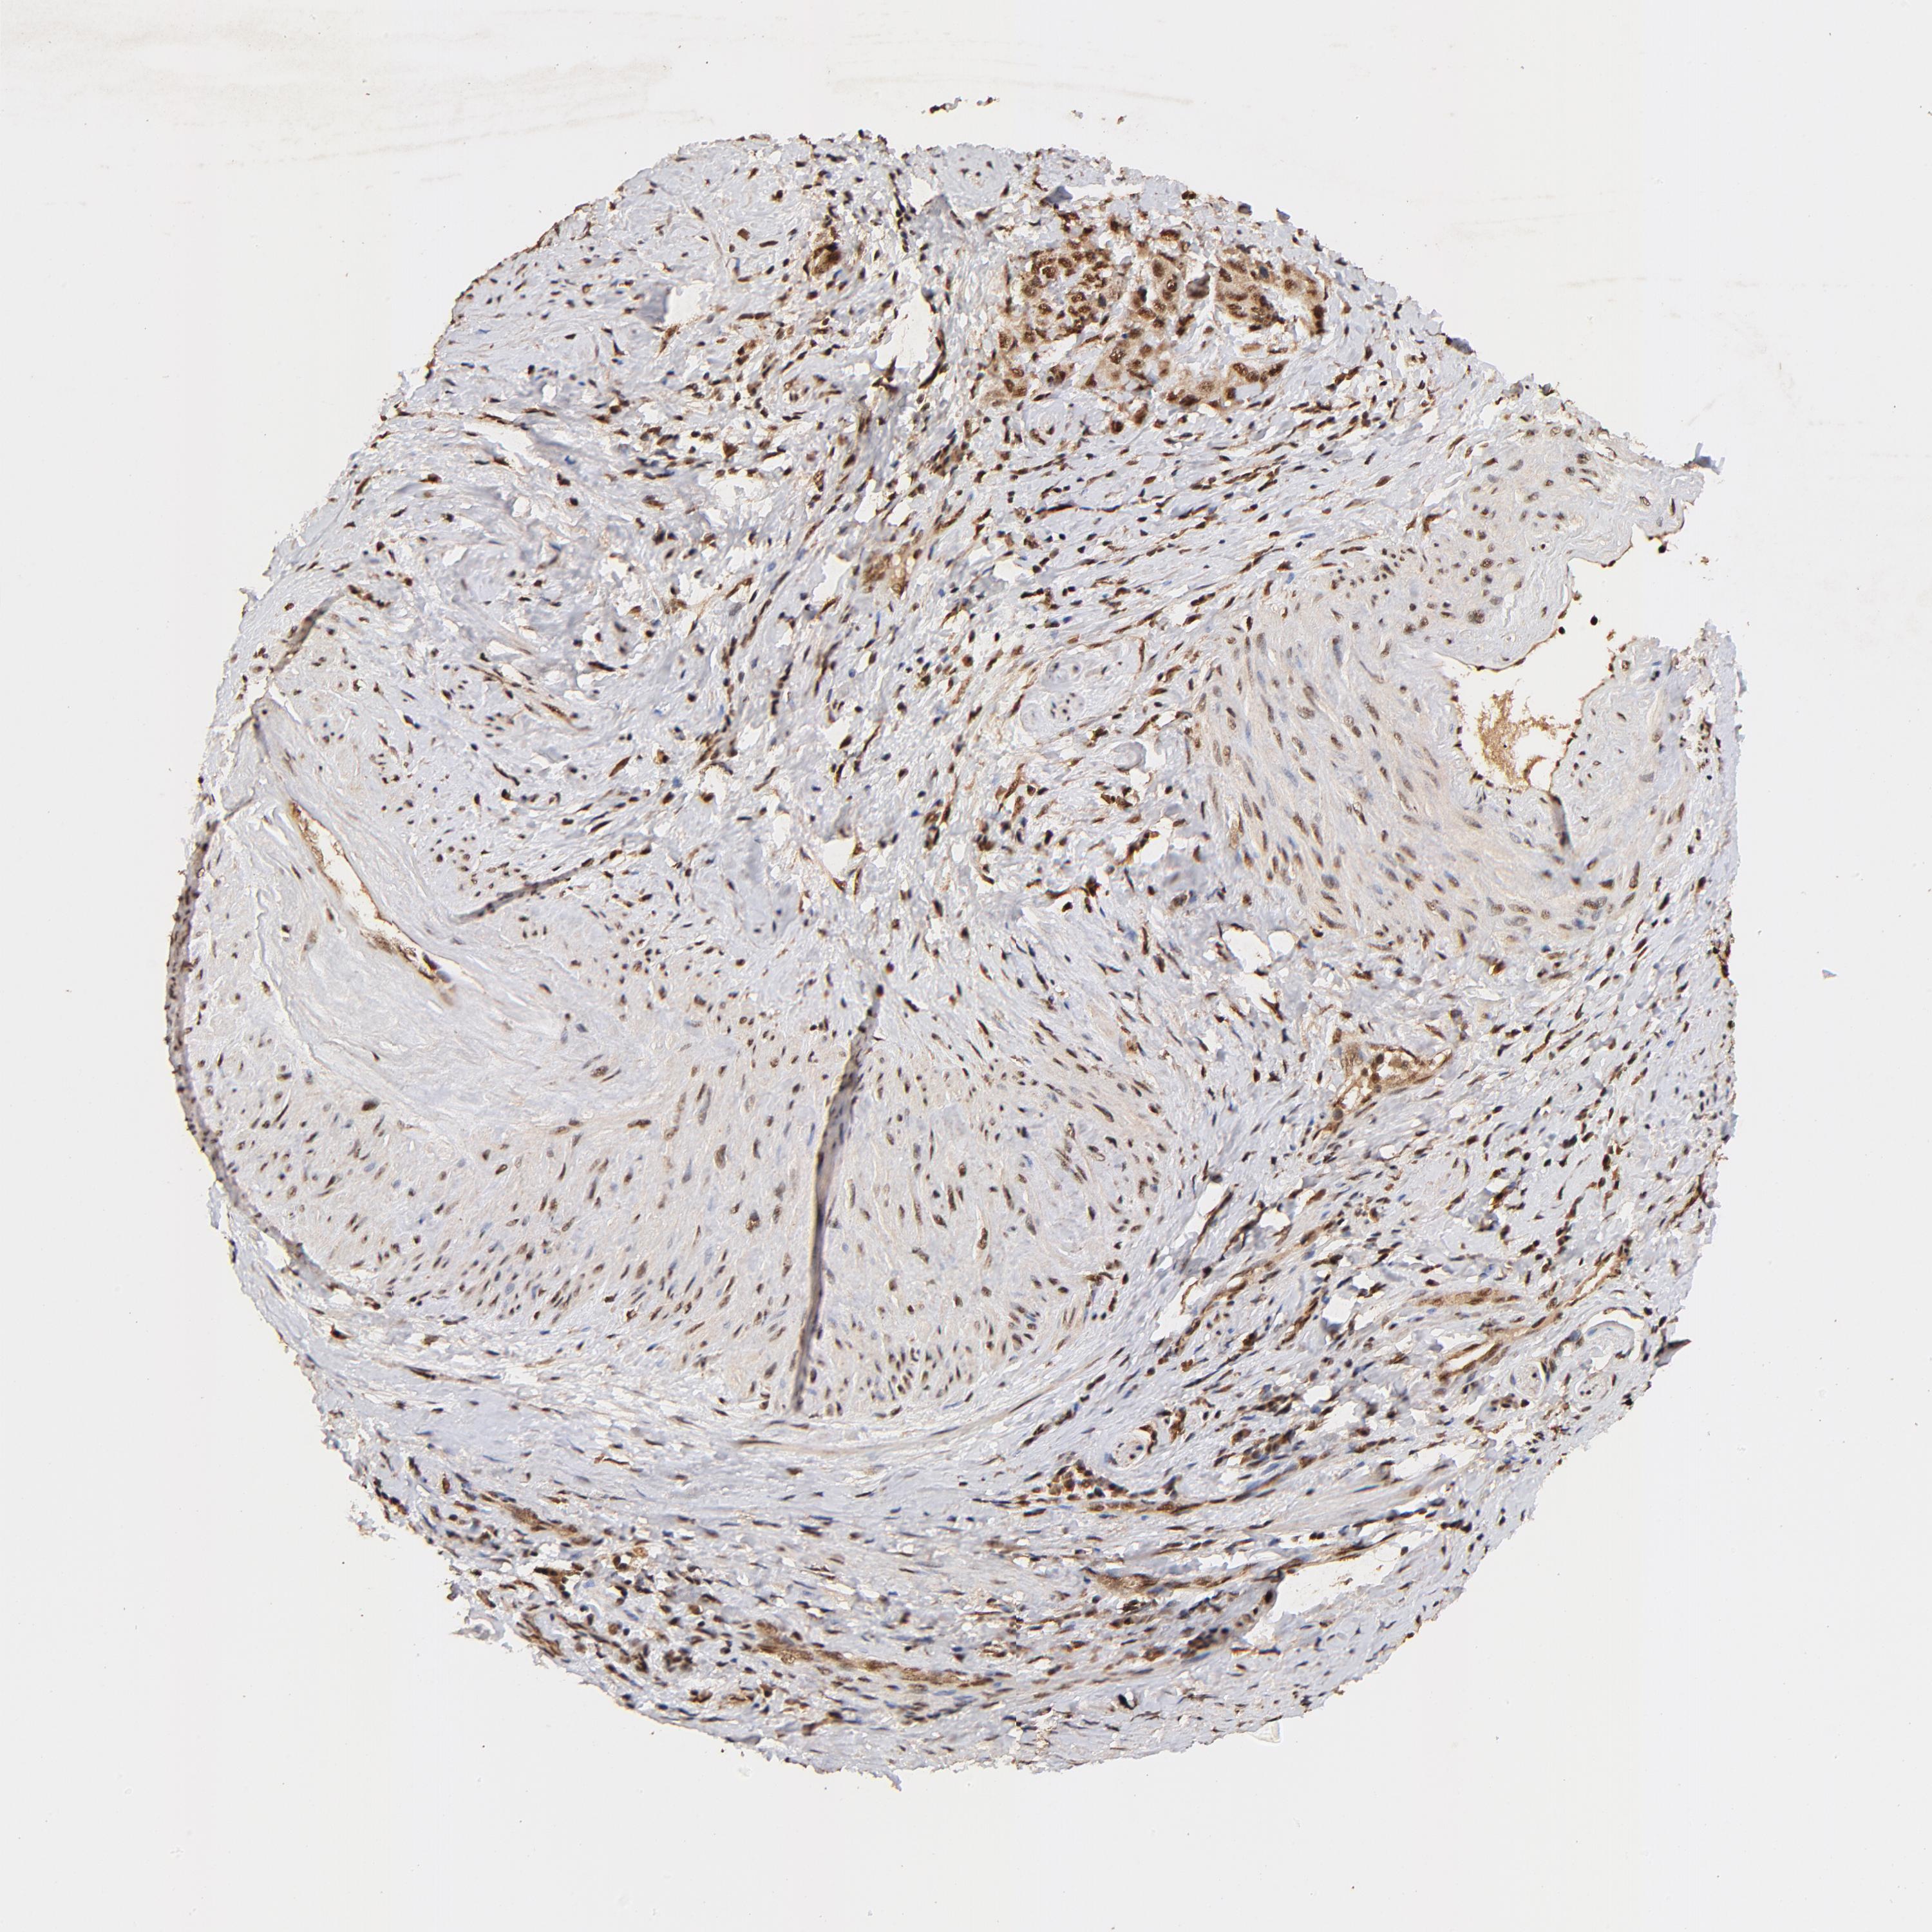

CERVICAL CANCER - Protein expressioni

A mouse-over function shows sample information and annotation data. Click on an image to view it in a full screen mode. Samples can be filtered based on level of antibody staining by selecting one or several of the following categories: high, medium, low and not detected. The assay and annotation is described here.

Note that samples used for immunohistochemistry by the Human Protein Atlas do not correspond to samples in the TCGA dataset.

Antibody stainingi

Antibody staining in the annotated cell types in the current human tissue is reported as not detected, low, medium, or high, based on conventional immunohistochemistry profiling in selected tissues. This score is based on the combination of the staining intensity and fraction of stained cells.

Each image is clickable and will lead to virtual microscopy that enables deeper exploration of all samples and also displays staining intensity scores, fraction scores and subcellular localization as well as patient and tissue information for each sample.

Antibody HPA003184

Antibody HPA003185

Staining

High

Medium

Low

Not detected

Intensity

Strong

Moderate

Weak

Negative

Quantity

>75%

75%-25%

<25%

None

Location

Nuclear

Cytoplasmic/membranous

Cytoplasmic/membranous,nuclear

Squamous cell carcinoma, NOS